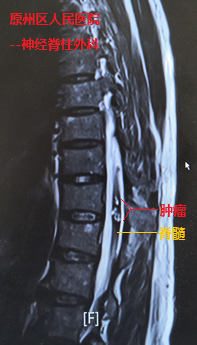

经检查发现,在史伯伯前后径不到1cm的胸椎脊髓内,却有直径约为1.5cm的肿瘤,并随着出血膨胀,几乎占据了整个脊髓,导致患者一侧下肢近远端肌力完全丧失(0级),另一侧下肢也仅能勉强移动(2-3级)。当地医院神经脊柱外科主任万欣龙判断,史伯伯得的可能是脊髓髓内的海绵状血管瘤,如若不进行手术,随着肿瘤出血后脊髓水肿的加重,患者的病情将进一步加重。

我院神经外科援宁队员郑小斌在查看患者并详细阅片后,与万欣龙主任交流讨论时,考虑到患者管性肿瘤体积大,且生长时间长达十余年,导致该肿瘤与脊髓组织的黏连十分严重,最终决定采用显微镜下经脊髓外侧沟切开脊髓并暴露肿瘤。郑小斌介绍,术中对肿瘤与脊髓边界的分离是手术的关键,加上患者病情严重,手术操作既要精细轻柔,也需连贯稳定。经过2个多小时手术,万欣龙与郑小斌将肿瘤完整地从脊髓内切除,完整保留了脊髓的正常结构。鉴于肿瘤体积大,出血后脊髓水肿严重,郑小斌与万欣龙还将脊柱椎板切除减压,并进行内固定手术加强脊柱的稳定性,手术顺利完成。